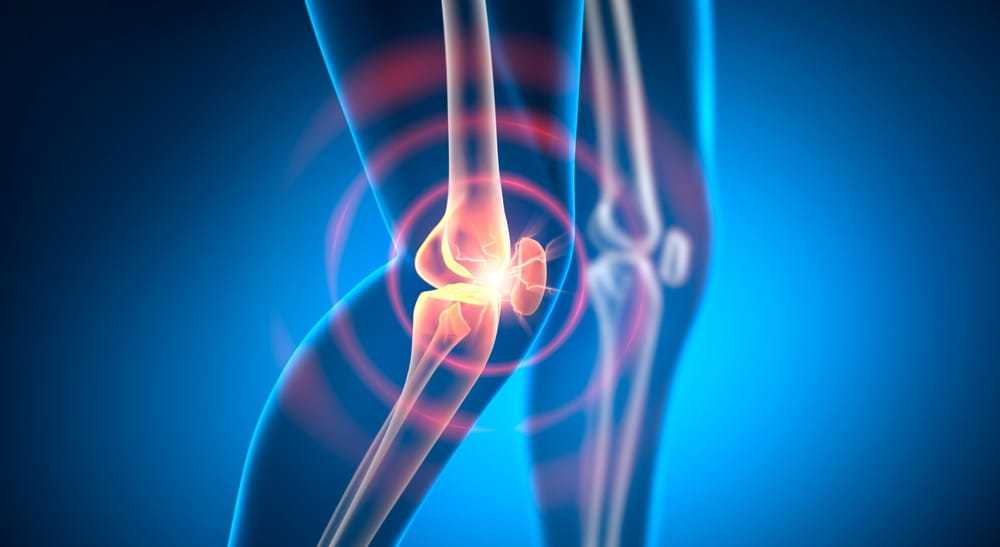

- زانو: شایعترین مفصلی که افراد در هوای سرد درد آن را تجربه میکنند، بهویژه در کسانی که آرتروز دارند.